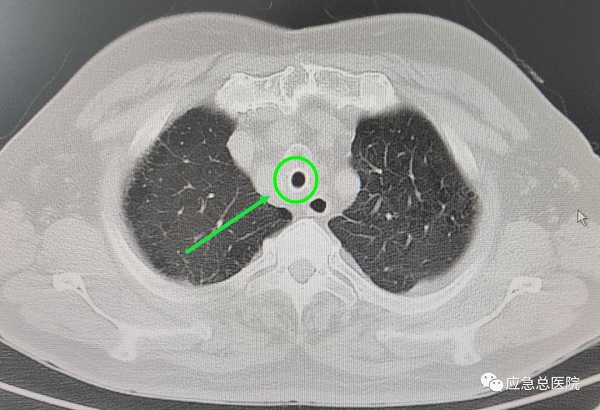

5天后,患者气管粘膜恢复,局部坏死物排出,再次气管镜局部治疗,清理管腔,经再次评估及精确测量后为患者放置了一枚气管硅酮支架,至此狭窄段管腔恢复至正常管径的80%,气喘症状完全缓解。患者激动地说:“能让王洪武教授这样的顶级专家亲自为我做手术,我太幸运了,是应急总医院给了我第二次生命啊!”